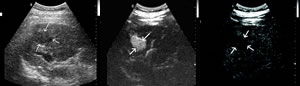

结果显示,96.6%(365/378个)原发性肝癌病灶的动脉相显示增强,其中 84.7% (320/378个)病灶增强早于肝实质(图a和b), 13.0% (49/378个)病灶增强与肝实质同步;增强方式中,87.0% (329/378个)病灶呈整体增强,9.3% (35/378个)呈斑片状增强,3.7% (14/378个)呈环状增强。在门脉相和晚期相,90.5% (342/378个)病灶相对于肝实质呈低增强(图c)。

图a 常规二维超声显示肝右叶一20 mm×15 mm稍低回声病灶(箭头所示),边界模糊

图b 注射超声造影剂SonoVue20秒后病灶显示整体增强(箭头所示),明显快于肝实质,且边界清晰

图c 注射超声造影剂SonoVue160秒后病灶回声减退(箭头所示),相对于肝实质呈低增强改变,符合典型的“快进快出”血流动力学表现。, 百拇医药